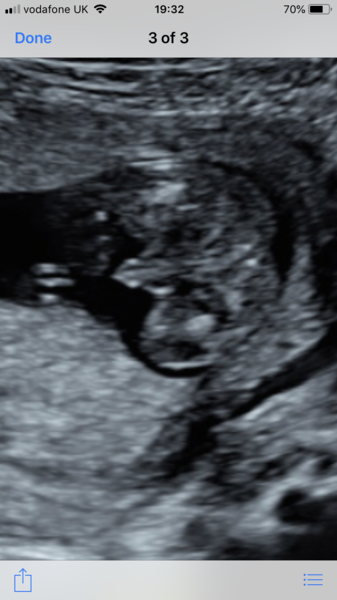

Emma0902 · 02/06/2018 10:25

Team pink 💖

The scan pics are so clear! She also gave us a little wave !!! So excited now counting down the days